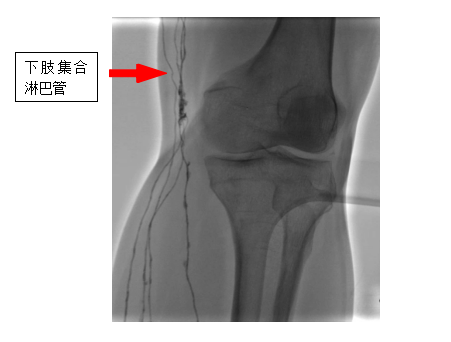

直接淋巴系统造影是一种先进的医学影像技术与手术的融合技术,它通过超显微技术将特殊的造影剂注入淋巴系统,在数字减影设备下使淋巴管及淋巴结清晰显影,从而能够精确诊断淋巴系统的回流障碍、漏出、返流、畸形等疾病,对于淋巴管瘤、淋巴水肿、乳糜漏、淋巴结转移癌等疾病的诊断和治疗具有重要意义。